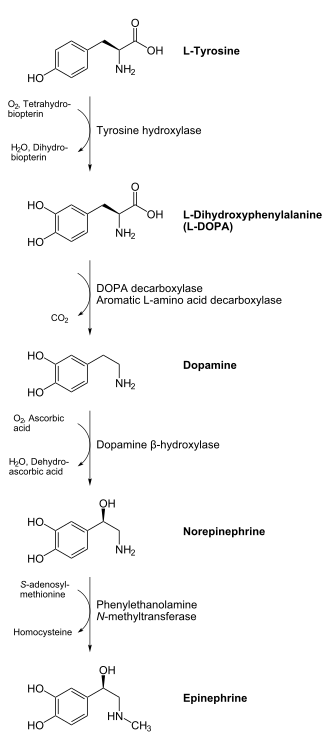

Levodopa is actually the precursor of dopamine and is part of a chain of reactions that lead to the synthesis of dopamine.

In the dopamine-producing neurons, tyrosine is first converted to levodopa by the enzyme tyrosine hydroxylase then the levodopa is converted to dopamine by the action of Aromatic L-amino-acid decarboxylase (AAADC)(also known as DOPA decarboxylase, DDC).

Levodopa can be taken by mouth and, unlike dopamine, crosses the blood brain barrier. But as it is easily denatured, it is usually taken in conjunction with carbidopa or benserazide which inhibit its decarboxylation (loss of the carboxly group, COOH, to produce dopamine) while it is still in the bloodstream. The proprietary preparation Sinemet is comprised of levodopa and carbidopa while Madopar is levodopa with benserazide. These adjuncts are known as DOPA decarboxylase inhibitors.